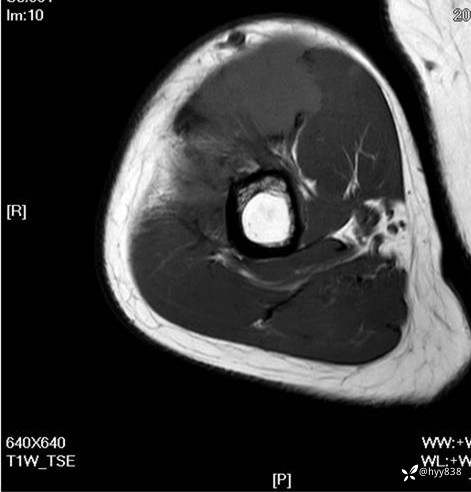

MRI AXI T1WI+T2WIfs

AXI T1WI+T2WIfs